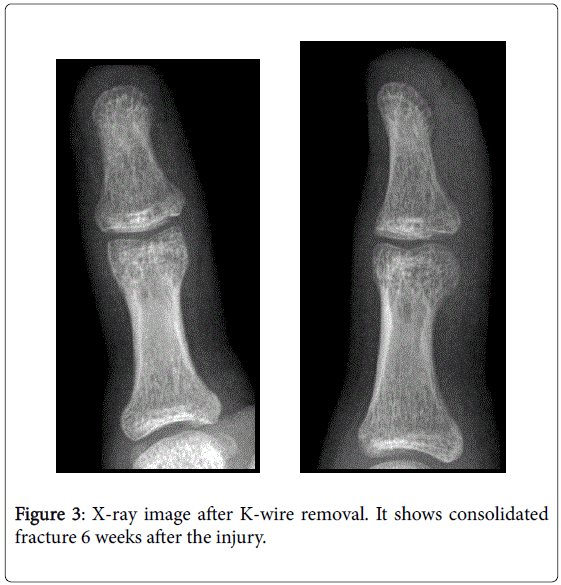

From www.omicsonline.org

The Ishiguro Technique for the Treatment of Adolescent Mallet Thumb Fracture OMICS International How Long For Mallet Fracture To Heal The healing time can vary depending on the severity of the injury and the treatment method. My # 1 advice to anyone who has a mallet finger is to keep the tip of the finger. Mallet finger usually happens when you jam your finger, such as by catching a ball. How long does it take for a mallet finger to. How Long For Mallet Fracture To Heal.